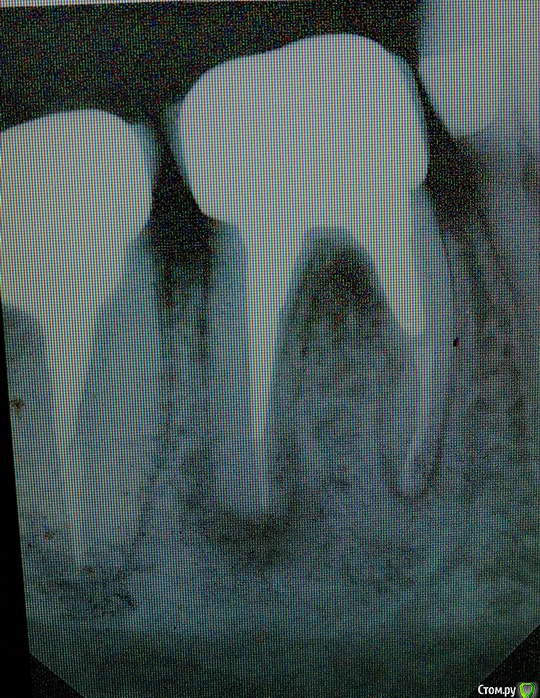

lejeboka Опубликовано 10 мая, 2018 Поделиться Опубликовано 10 мая, 2018 (изменено) Добрый день На днях сходил к стоматологу на контрольных осмотр и проф гигиену. Лечусь у нее с 2010 года, в общем доверяю. Результат расстроил.6-й слева снизу – на удаление.Зуб был депульпирован в 1990-м, в райполиклинике, спустя 2-3 года поставил коронку там-же. Успешно проходил с ней 17 лет, потом решил поменять на металлокерамику. Врач-ортопед ставить коронку отказался, т.к. были изменения на корнях.Переделали каналы. Спустя 6 лет – киста, культевую вкладку удалить нельзя, зуб на удаление. https://cloud.mail.ru/public/JuP9/LF2BUBPsG https://cloud.mail.ru/public/9mas/cnXZ2Ra6JСедьмой справа сверху – необходимо ставить коронку, т.к. пломба выпала, и качественно ее поставить нельзя. Зуб был депульпирован в 2011-2012 году лечащим врачом. Но нужно переделать один из каналов. https://cloud.mail.ru/public/7fhp/wFFS5S6S4 Седьмой снизу (рентгена нет) , справа, поставлена коронка 6 лет назад коронку надо менять, т.к. десна опустилась. Вопрос 1: нормально ли это, что спустя 5-7 лет после депульпирования нужно переделывать каналы, а после ревизии каналов зуб идет на удаление? Каналы были запломбированы хорошо, в чем тогда проблема, в стерильности при работе?Прошу прощения перед доктором, если она вдруг читает этот форум.Еще у нас был пропущеный канал на одном из зубов и киста. В след четверг записался на удаление левой нижней шестерки.Вопрос 2, извините если слишком ламерский. Как я понимаю, при удалении зуба при планах на последующую имплантацию иногда в лунку добавляют какой-то материал для того, что бы кости было больше. Это нужно обсуждать с доктором перед удалением? Доктору нужно будет передать рентгеновский снимок? Вопрос 3: правильно я понимаю, что на корнях 7-ки снизу слева то-же есть проблемы? Изменено 10 мая, 2018 пользователем lejeboka Ссылка на комментарий